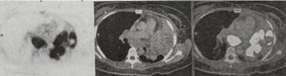

August 2025 chest CT scan identified two new left lung lesions. with normal CA-125 and AFP, but with high LDH (339 U/L). PET-CT scan (19 September 2025) showed a l10.4 x 5.9 x 8.3 cm heterogeneously enhancing, hypermetabolic soft tissue mass in the left upper lung lobe, causing severe narrowing of the distal left main bronchus and encasing the left lobar arteries. Another 3.6 cm mass was noted in the left lower lung lobe. Progression of hypermetabolic subcarinal, paratracheal, and para-aortic lymph nodes, was worrisome for nodal metastasis (Figures 1 & 2).

Figure 1: Axial PET-CT scan correlating the intense FDG-avidity on the PET slice (left) with the large, heterogeneously enhancing soft tissue mass seen in the left upper lobe (middle and right).